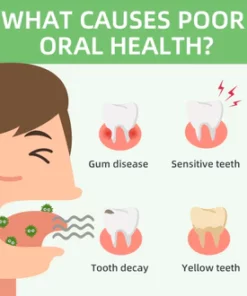

What Causes Poor Oral Health?

Every day, food residues in our mouths create a breeding ground for various bacteria and microorganisms within the oral cavity. This can result in a range of oral health issues, including bad breath, mouth ulcers, yellow teeth, cavities, calculus buildup, gum inflammation, bleeding gums, tooth sensitivity, weakened or missing teeth, swollen gums, toothaches, loose teeth, tooth loss, and even the risk of oral cancer.

As these conditions worsen, you may experience persistent bad breath, gum inflammation, and other problems. Bacteria continue to harm your gums, leading to issues like bleeding, pain, and redness. Without timely intervention, these oral problems can escalate, potentially causing periodontitis, dental plaque, dental calculus, loose teeth, tooth pain, and eventually tooth loss.

What Problems Could Poor Dental Health Cause?

- Oral diseases, while largely preventable, pose a major health burden for many countries and affect people throughout their lifetime, causing pain, discomfort, disfigurement, and even death.

- It is estimated that oral diseases affect nearly 3.5 billion people.

- Untreated dental caries (tooth decay) in permanent teeth is the most common health condition according to the Global Burden of Disease 2019.

- Treatment for oral health conditions is expensive and usually not part of universal health coverage (UHC).

- Most low- and middle-income countries do not have sufficient services available to prevent and treat oral health conditions.

- Oral diseases are caused by a range of modifiable risk factors common to many noncommunicable diseases (NCDs), including sugar consumption, tobacco use, alcohol use poor hygiene, and their underlying social and commercial determinants.